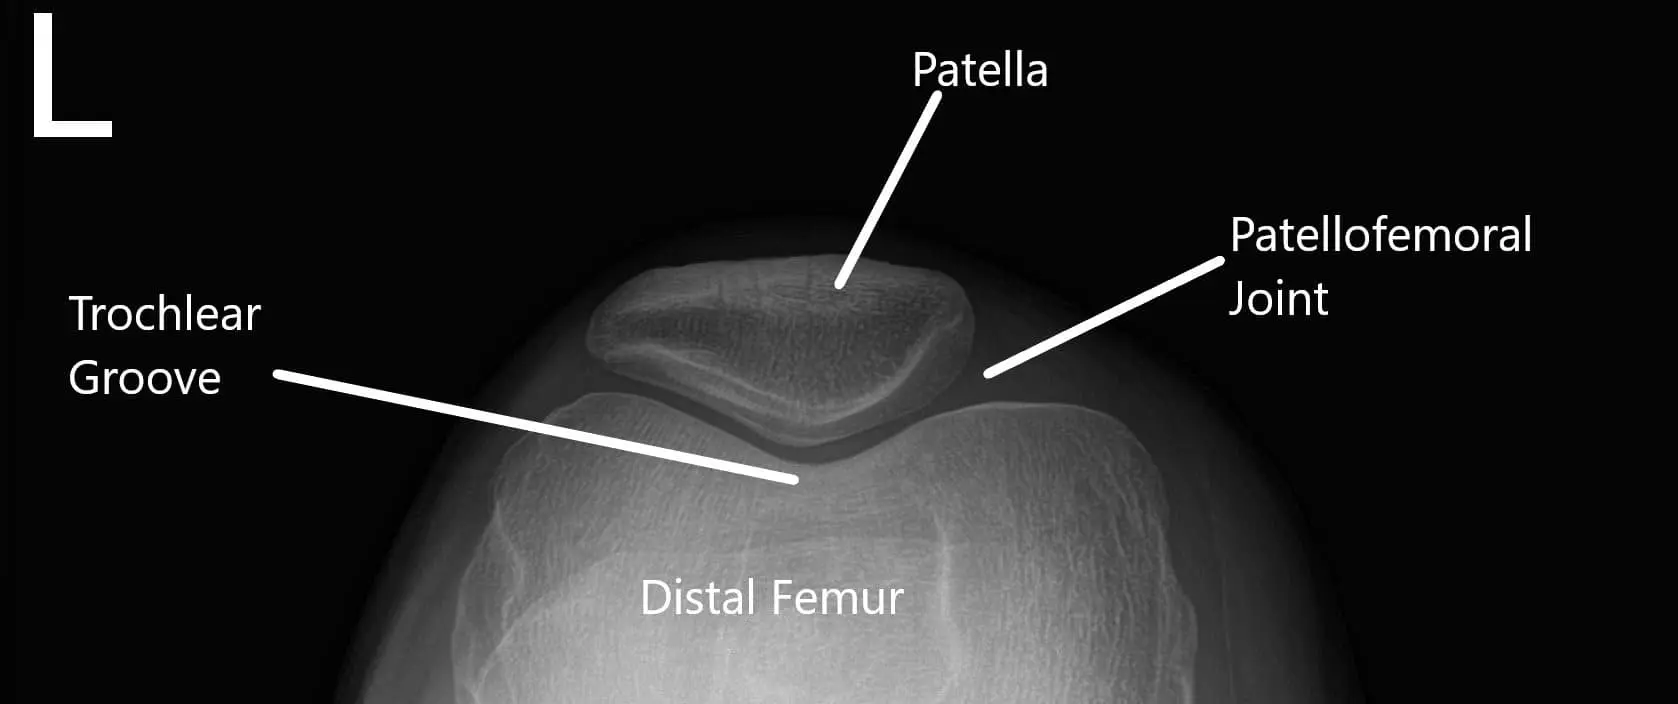

X-ray of the knee in AP and skyline view.